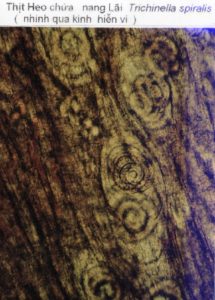

TRICHINOSE (bệnh giun bao), cũng là một bệnh ký sinh rất quan trọng trong thịt, gây nên bởi giun lãi Trichinella spiralis. Một số gia súc như chó, mèo, heo, ngựa cũng như một số thú rừng như chuột, chồn, gấu, v.v… đều có thể bị bệnh trichinose. Ấu trùng nằm cuộn tròn trong những nang nhỏ trong thịt, không thể thấy bằng mắt thường được.

Heo bị nhiễm bệnh do ăn phải các thức ăn bẩn, hoặc ăn nhầm xác chuột có chứa ký sinh trùng. Ăn phải thịt heo bệnh, nếu nấu không thật chín, chúng ta sẽ bị bệnh trichinose. Chất acide trong bao tử sẽ làm tan các vỏ nang và giải phóng ấu trùng Trichinella spiralis ra ngoài.

Nếu bị nhiễm nhẹ thì không thấy có triệu chứng gì cả. Nếu khá nặng, bệnh nhân sẽ bị mệt mỏi, đau nhức các bắp thịt và các khớp xương, mí mắt sưng phù và có thể nhức nhối trong nhãn cầu. Trường hợp nặng hơn nữa thì có thể có biến chứng tim và não.

Bệnh Giun bao trichinose